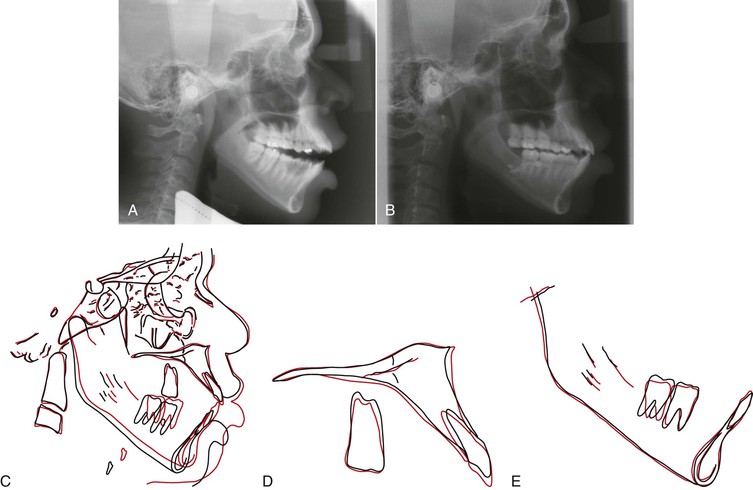

To achieve additional vertical correction of the anterior segments, the functional occlusal plane must be modified by using either a clockwise (steepening) or a counterclockwise movement. Steepening the occlusal plane can be somewhat easily achieved, although it is rarely desired. The reverse movement (counterclockwise rotation) is often indicated in skeletal open bites (Fig. 9-31) but unfortunately it can rarely be achieved by orthodontic means only. The long face patient with adequate or excessive gingival display and an anterior open bite is a good example of a patient for whom a counterclockwise rotation of the mandibular occlusal plane is recommended (Fig. 9-32). In this type of patient the upper incisors should be maintained or intruded and the upper occlusal plane should be either intruded or rotated in a clockwise direction.

Figure 9-31 A, Pretreatment lateral cephalogram. B, Posttreatment lateral cephalogram. C-E, Superimposition showing counterclockwise rotation of the lower occlusal plane by intruding the lower molars via use of skeletal anchorage only in the lower arch. The net result is anterior open-bite reduction with mandibular autorotation.